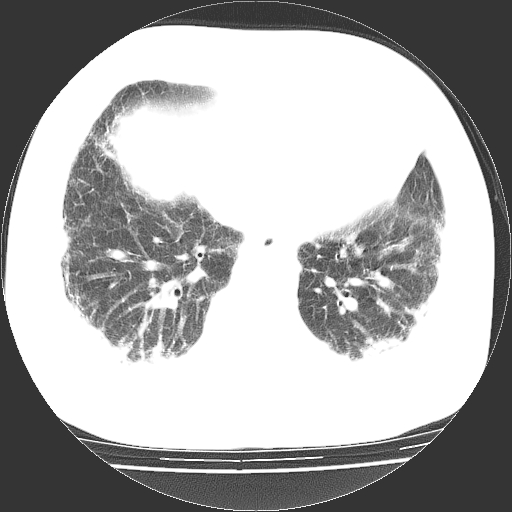

男,68岁,咳嗽、胸闷、发烧三天,查体:双肺散在湿罗音。

依据:1、两肺广泛条索状、网格状、蜂窝状改变。

1.双肺间质纤维化并感染;

2.双肺慢支炎肺气肿;

3.支扩并感染;

4.肺原性心脏病;

5.双侧胸腔少量积液;双侧胸膜增厚。

双肺多发条索状、网格状及小灶状密度增高影。考虑慢支合并感染.间质纤维化,双侧少量胸腔积液

两肺广泛条索状、网格状、蜂窝状改变。肺间质纤维化,肺心病,双侧胸腔积液